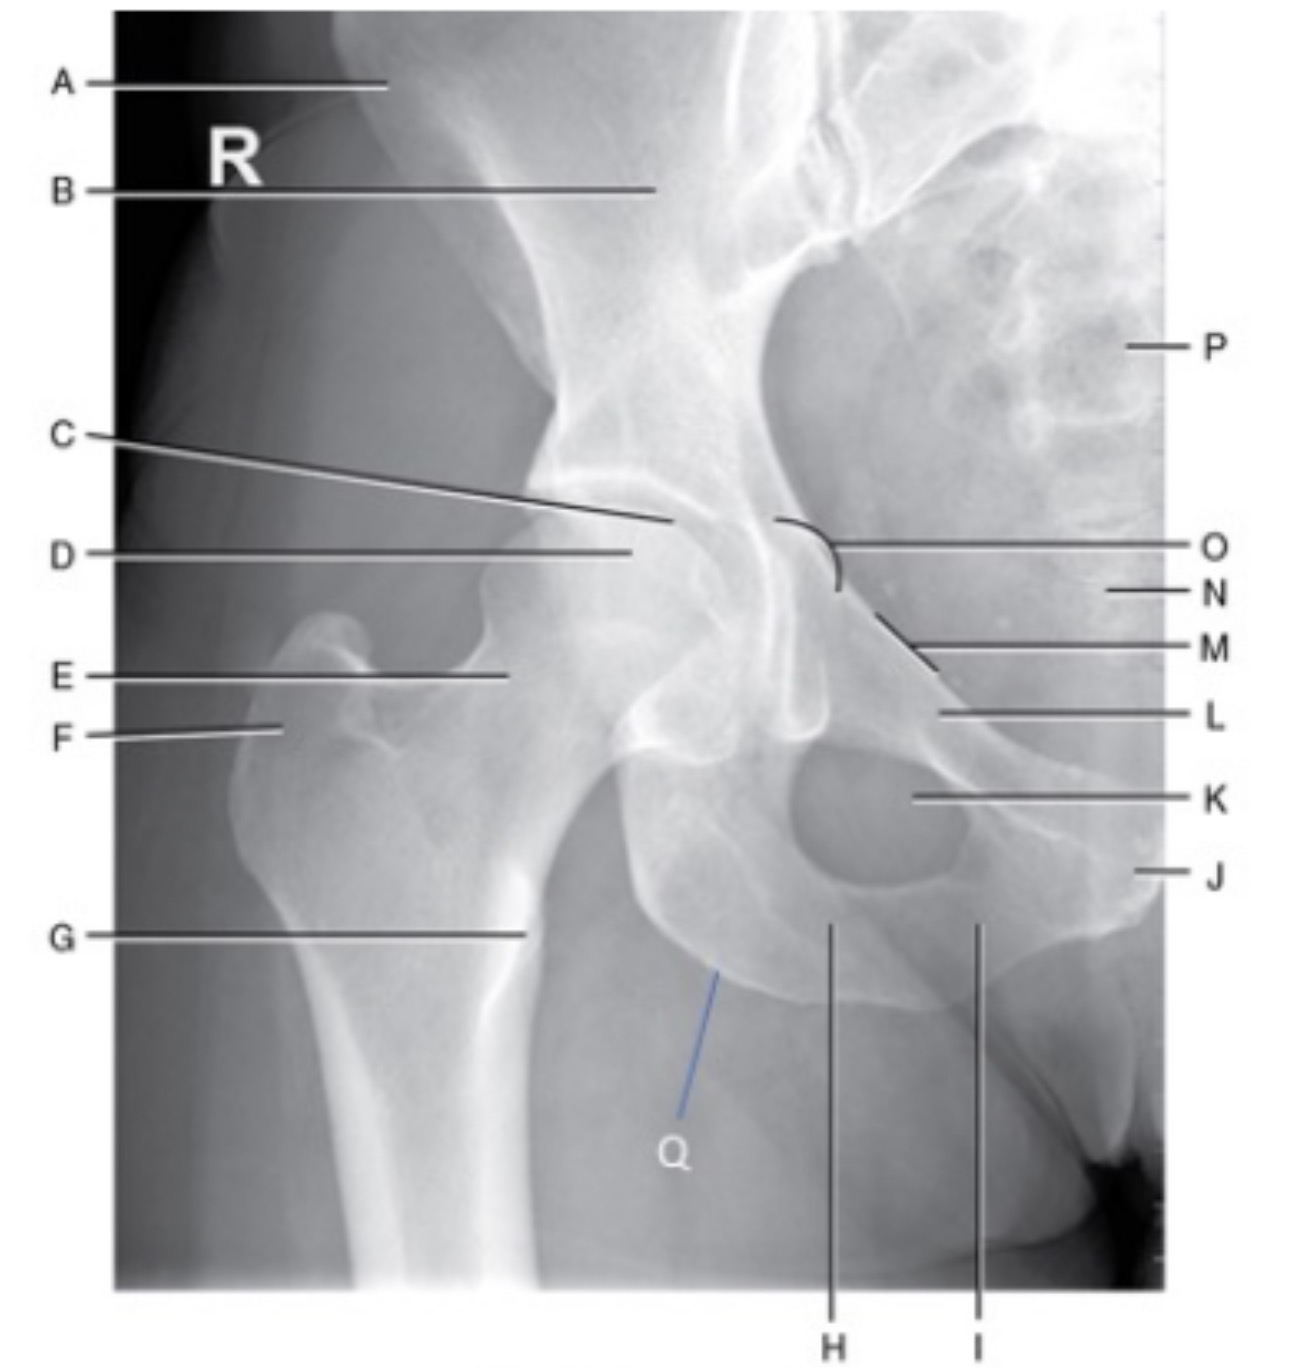

Name Area A and B

A. Right Anterior Superior Iliac Spine

B. Right Body of Ilium

Name Area C and D

C. Right Acetabulum

D. Right Femoral Head

Name Area E and F

E. Right femoral neck

F. Right greater trochanter

Name Area G

Right lesser trochanter

Name H and I

H. Right Ramus of Ischium

I. Right inferior ramus of pubis

Name Area J and K

J. Pubic symphysis

K. Right obturator foramen

Name area L and M

L. Right superior ramus of pubis

M. Pelvic rim

Name area N and O

N. Coccyx

O. Right ischial spine

Name area P

Sacrum

Name Q

Right ischial tuberosity